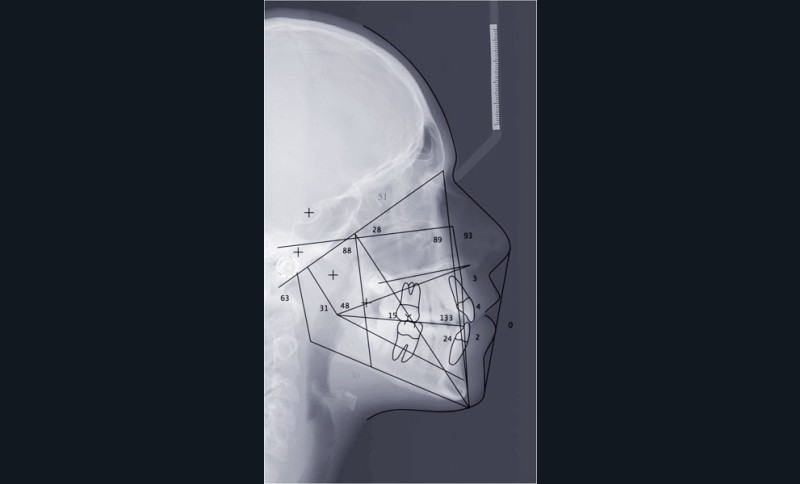

Le cas d’Anthony âgé de 11 ans et 7 mois qui présente une endomaxillie bilatérale associée à un léger encombrement mandibulaire dans un contexte de classe I squelettique hyperdivergente (fig. 1 à 10) est très représentatif de ce que peuvent apporter les forces légères appliquées aux alvéoles dentaires tout en intégrant des torques spécifiques qui permettent de contrôler parfaitement l’orientation radiculaire (fig. 11 à 29).